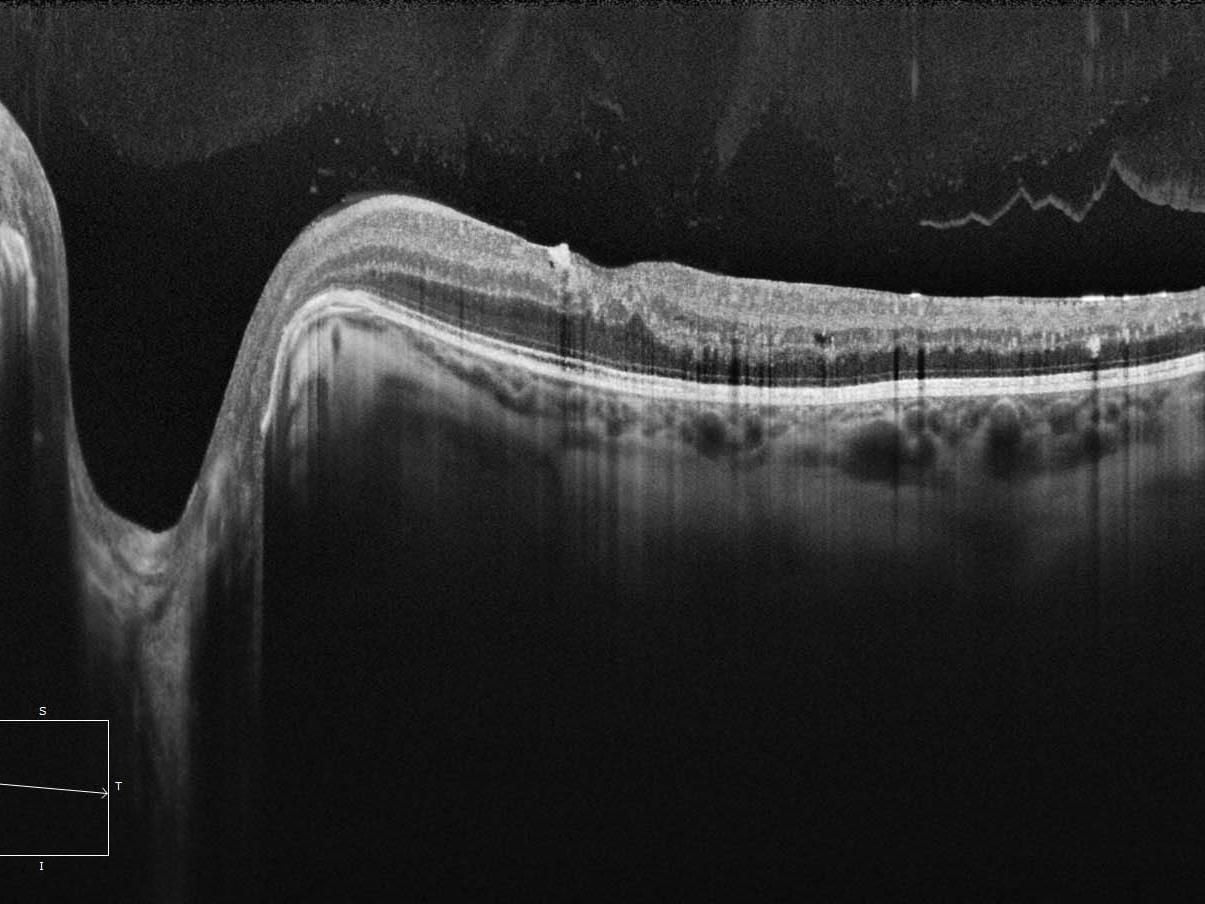

ZEISS Cirrus OCT Retinal Eye Check Latest in Eye Health Care

Measures the layers of the back of the eye to pick up early warning signs before they

affect your vision.